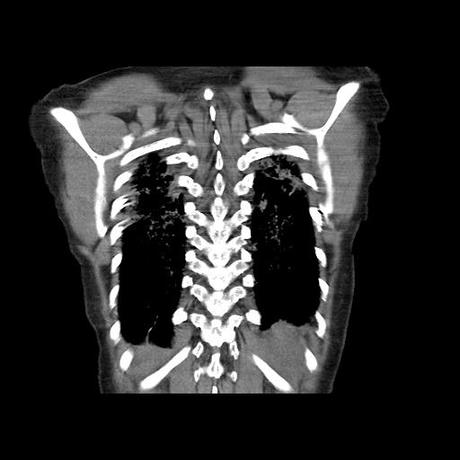

Se realiza volumen de tórax en fase simple, desde los opérculos torácicos hasta los hemidiafragmas, observándose:

El parénquima pulmonar con areas parcheadas difusas en vidrio despulido combinadas con otras areas hipodensas de baja atenuación debidas a atrapamiento aéreo y engrosamiento intersticial y zonas de fibrosis de predominio en lóbulos medios e inferiores de ambos pulmones.

- LOS HALLAZGOS PUEDEN ESTAR EN RELACIÓN A NEUMOPATIA INTERSTICIAL PROBABLE ETIOLOGIA HIPERSENSITIVA VS AUTOINMUNE/BACTERIANA/FUNGICA.